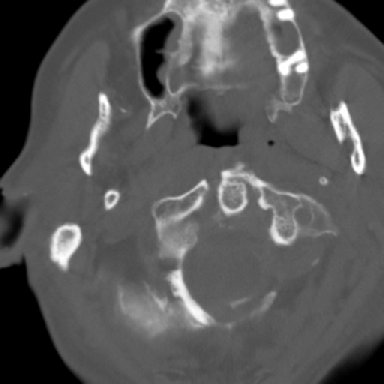

Return to Jefferson Fracture